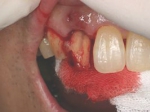

前歯即時埋入症例

術前術前主訴-前歯が腫れて痛い。治療法のうち、ブリッジとインプラントを説明して隣の前歯を削らないですむことからインプラントを選択された。 術前レントゲン術前レントゲン術前レントゲン 抜歯抜歯抜歯を行う。折れていた位置がかなり深い位置であるのがわかる。 歯根も抜歯歯根も抜歯

歯根も抜歯歯根も抜歯歯根も抜歯 抜歯した穴をよく掃除抜歯した穴をよく掃除抜歯した穴をよく掃除(掻爬)後すぐにインプラントを埋入 埋入直後のレントゲン埋入直後のレントゲン埋入直後のレントゲン。上部に見えるのは抜いた歯を利用して両どなりの歯に接着して一時的に使えるようにした。 二次オペ時二次オペ時

仮の支柱を装着仮の支柱を装着仮の支柱を装着 作業模型上のセラミック上部構造作業模型上のセラミック上部構造作業模型上のセラミック上部構造 術後術後術後